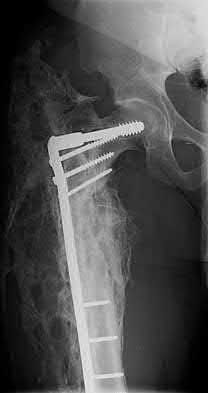

3. # Which of the following is not an appropriate implant for treatment of the fracture seen in Figure A?

The image shows a reverse obliquity intertrochanteric hip fracture.

According to the referenced article by Haidukewych et al, unstable peritrochanteric hip fractures have a worse outcome (failed in 9/16 cases) if treated with a sliding hip screw. Two additional factors that were found to have a strong correlation with postoperative failure (nonunion, loss of reduction) were poor reduction and poor implant placement. In this study, fixed angle devices were superior. Intramedullary fixation has the added advantage of a shorter lever arm and less potential for fracture collapse and limb shortening.

The IMN also acts as a medial buttress.

According to Sanders et al, the dynamic condylar screw (DCS) can also be used in subtrochanteric models, but should not be used if extensive comminution is seen, as they reported a high failure rate with DCS in these fractures if highly comminuted. They report a 77% overall union rate with this device.